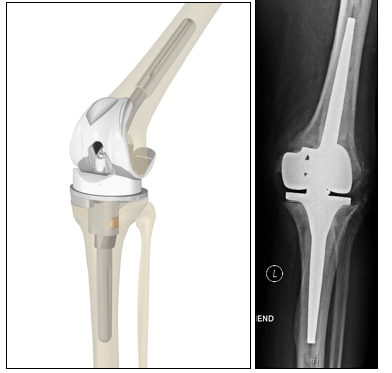

Abbildung 1 a–b:

a) Schematische Darstellung des Kniegelenkes (Fa. Aesculap)

b) Arthrose mit aufgefasertem Gelenkknorpel am Oberschenkel (Pathologisches Institut der Charité Berlin)